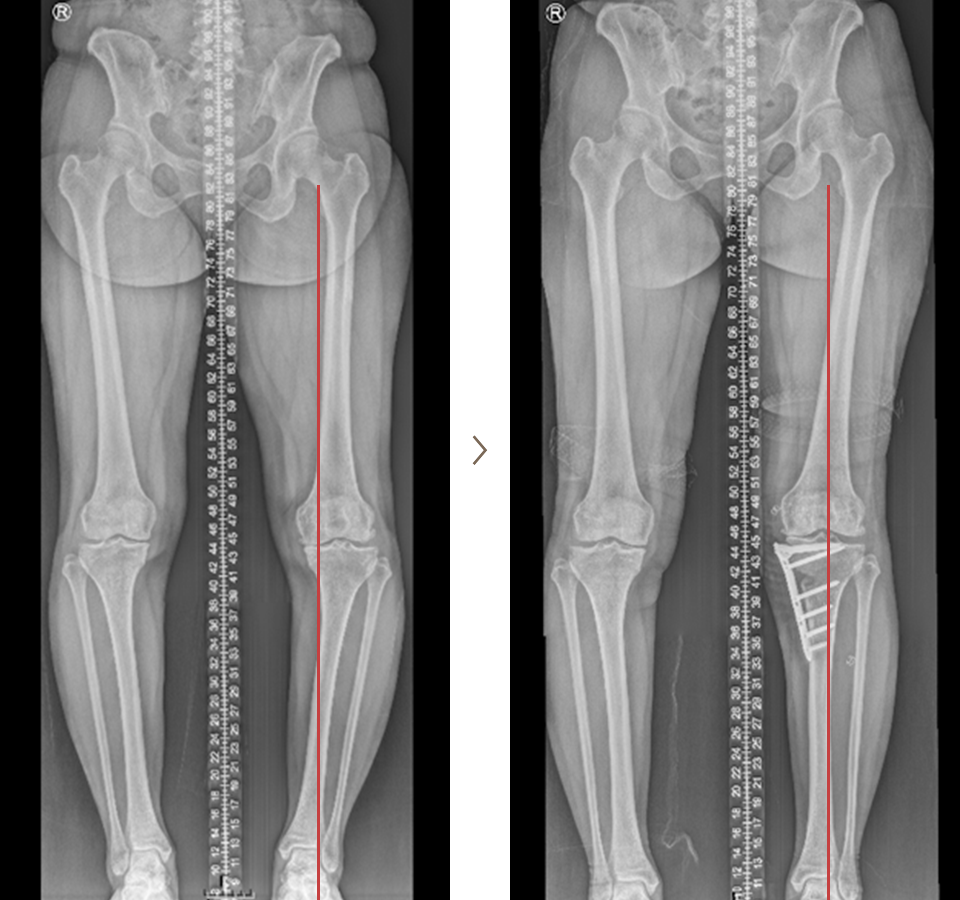

휜다리 교정술 치료 사례

- 환자 동의하에 게시된 이미지입니다.

<수술전 엑스레이 사진>

<수술후 엑스레이 사진>